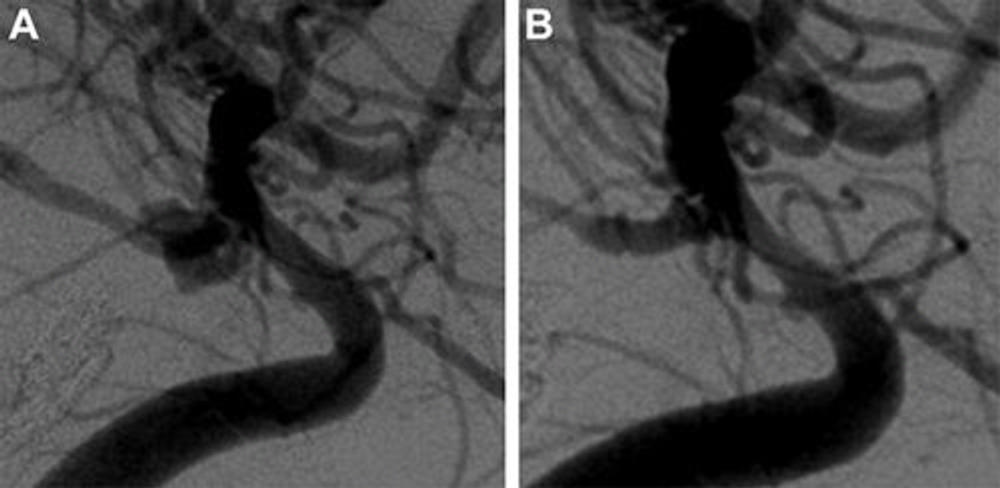

Figure 2. Digital subtraction angiography images show basilar tip aneurysm (A) before and (B) at last follow-up after Woven EndoBridge device placement.